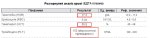

Нужно сдать для выписки РОА: ОАК, глюкоза, АСТ, АЛТ, билирубин, холестерин, ИЗФ, ТТГ, Т3, Т4, АТ-ТПО.

Чет лень гуглить каждый анализ, вы явно эксперты в этом - какие общие требования к сдаче этих анализов? Не есть за 12 часов? Не дрочить? Не заниматься спортом? Может стоить за пару дней сесть на какое-то особое питание, чтобы анализы были лучше и точно выписали таблы. Короче подскажите пожалуйста..

Чет лень гуглить каждый анализ, вы явно эксперты в этом - какие общие требования к сдаче этих анализов? Не есть за 12 часов? Не дрочить? Не заниматься спортом? Может стоить за пару дней сесть на какое-то особое питание, чтобы анализы были лучше и точно выписали таблы. Короче подскажите пожалуйста..

За 2 дня до не есть «вредное» и жирное

За 12 часов не есть, лучше утром сдавать до 12 дня

Раз щитовидку чекают то спорт убери на 2 дня до анализа. За день до анализа не жри сильно жирное, в последний прием пищи вообще нихуя жирного не должно быть. Часов 10 не ешь и с утра сдаешь

Вот, что мне врач выписала перед роа, но я бы еще сдала анализы на глюкозу, ТТГ и ОАК